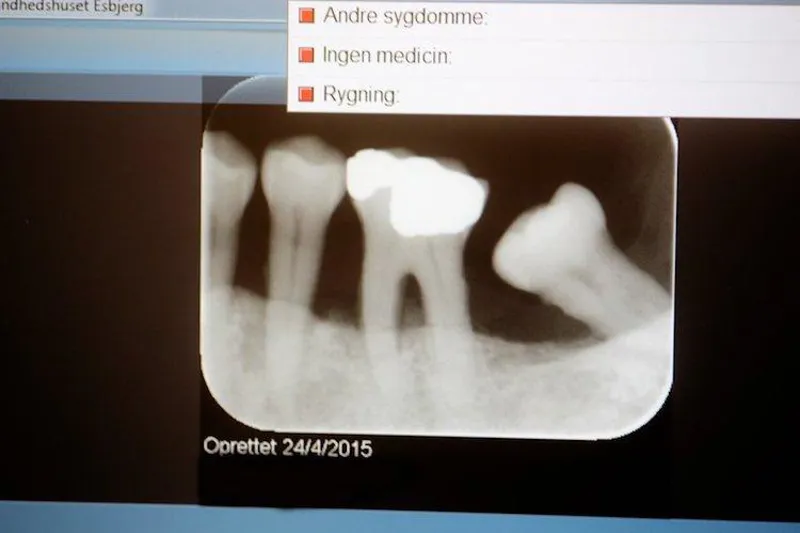

Kan det betale sig at foretage regenerativ behandling på en tand med fremskreden parodontitis, eller er det bedre at ekstrahere tanden og erstatte den med bro eller implantat?

Dette relevante spørgsmål har italienske forskere søgt at besvare i en randomiseret kontrolleret klinisk undersøgelse med 10 års opfølgning. 50 patienter, som havde en tand med vertikalt fæstetab til apex, blev fordelt på to grupper.

I kontrolgruppen blev den kritiske tand ekstraheret og erstattet med tand- eller implantatunderstøttet fast protese, mens der i testgruppen blev foretaget regenerativ kirurgi (membranbehandling) af den kritiske tand. 10-årsoverlevelsen var 100 % i kontrolgruppen og 88 % i testgruppen; men forskellen var ikke statistisk signifikant (p = 0,08).